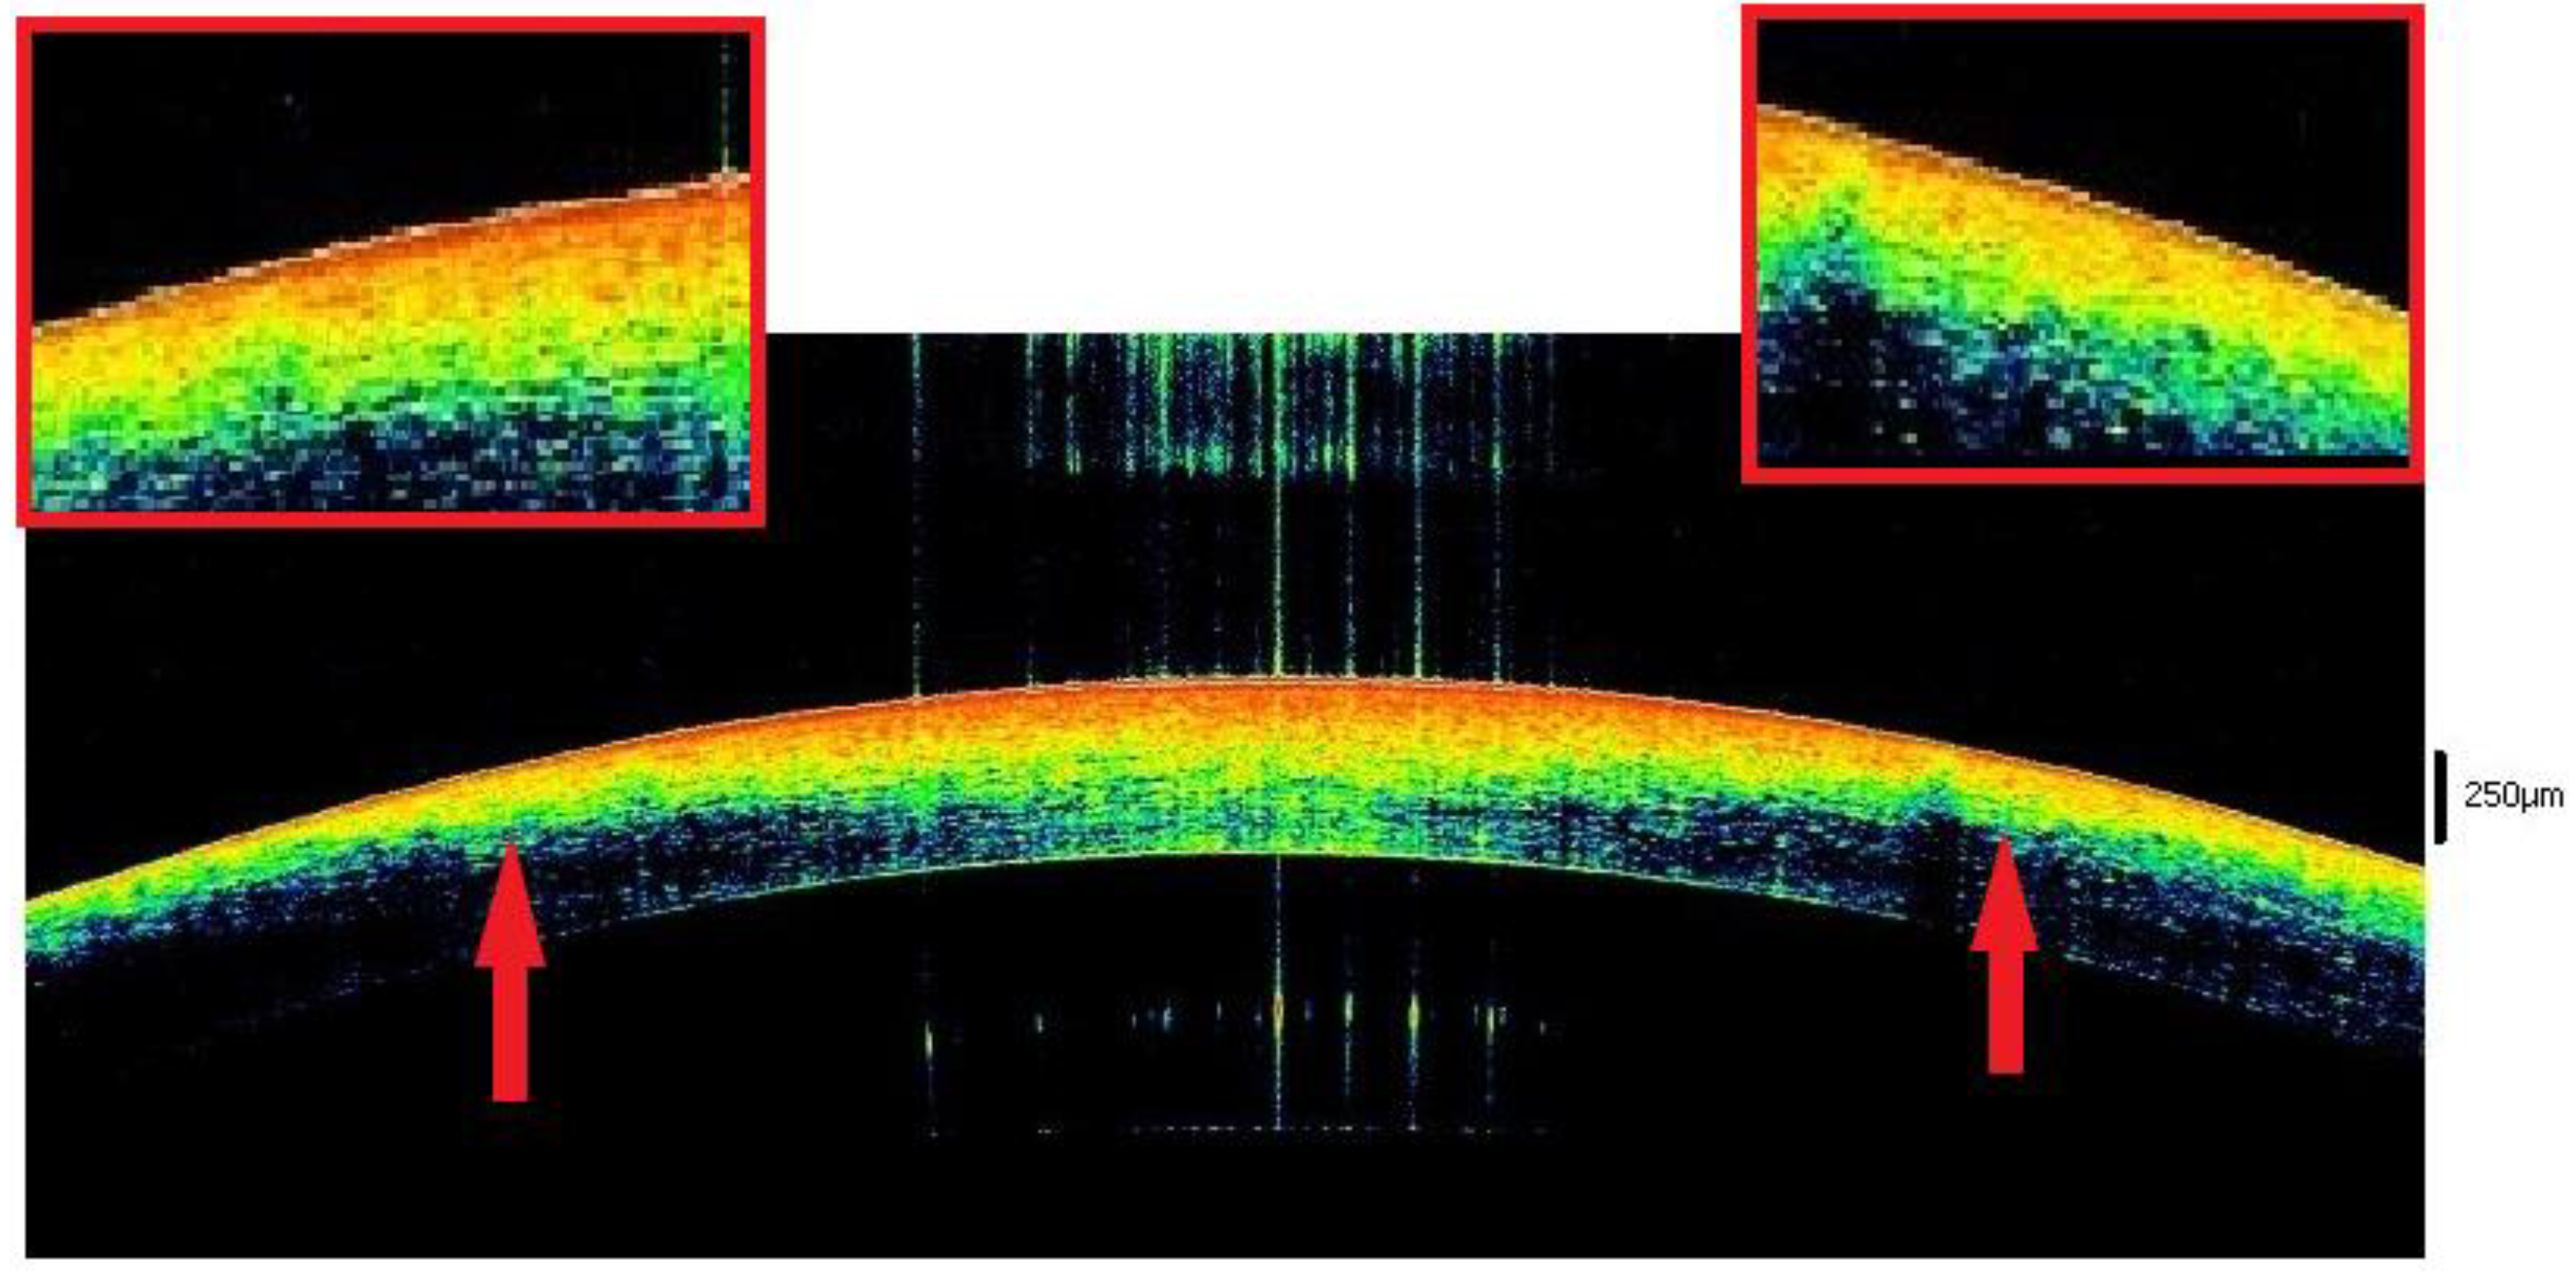

| 3–6 | Lacrimal tear disappears. Binary sign with hyperreflectivity of the outer and inner layer and hyperreflectivity in the middle. | Posterior waves (Nioi Napoli sign grade 0). Thickening of the stroma with initial differentiation between posterior and anterior tissue. In 69,5%, the posterior stroma assumes a wavy morphology. | Hyperreflective respect to the posterior stroma. Presence of Endothelial spots | V-shapes in 56.5% of cases. Nioi–Napoli I (21.7%) |

| 6–9 | Appears like a single, hyperreflective layer in 50% of cases. In 50% ‘binary morphology’. | Differentiation between anterior hyperreflective and posterior hypo-reflective stroma in 56.5% of cases. Presence of one tissue peak that protrudes in the anterior chamber (Nioi-Napoli 1) | Hyper-reflectivity with the presence of multiple spots. | Nioi–Napoli II (21.7%). Initial loosing of the spheric form of the tissue.in 34.7% of cases |

| 9–12 | Single hyperreflective layer in 91.3% of cases. In the 8.7% initial flaking of the epithelium. | Thickening of the stoma. Anterior-posterior differentiation in 100% of cases. Waving with one of two protruding peaks in 14 cases (60.8%). | Unchanged | Nioi–Napoli III (60.8%) |

| 12–17 | Single hyperreflective layer in 100%. Epithelium flacking in 34.7% of cases. | Important thickening, structural inhomogeneity with anterior-posterior differentiation and multiple hyporeflective spots. Posterior waving with more than two peaks in 100% of cases. | Hyperreflective. | Nioi–Napoli IV in 100% of cases. Stromal Striae in 60.8% of cases. |